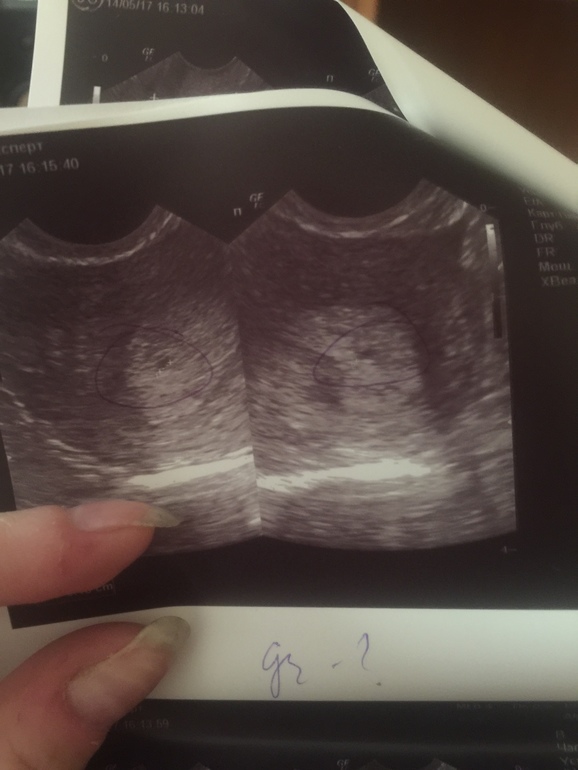

Кровь не сдавала, была на УЗИ, и тесты делала

Добрый день, у меня тоже вот 5я неделя, УЗИ вам показало пя?)

Показало мою малютку))

Я вас поздравляю) лёгкой беременности)) у меня показало только вагинально, вот переживаю нормально ли, что так пока не видно( может срок маленький, я первый раз, поэтому и срок даже толком не могу вычеслить( и узист не нормальный попался(

Видно вашу точечку, просто срок маленький и ля-ля тоже ))

У меня тоже вагинально делали ))

У меня так было в 5 недель, правда больше с правой стороны кололо. Так себя накрутила, что это внематочная, что побежала на УЗИ :) Не опытная, это моя первая Б